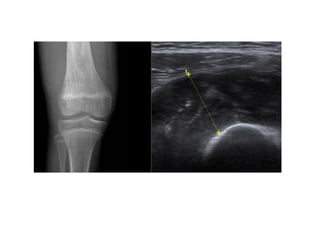

RAYOS X

Disminución del espacio articular

Asimétrica, medial > lateral

Esclerosis subcondral

Quiste subcondral

Osteofitos

Cuerpos libres

Etapas avanzadas:

Deformaciones articulares Heberden nodes

and Bouchard nodes

Subluxación articular

HALLMARK´S RADIOLOGICAL FEATURES

AP y lateral

Pérdida del espacio

articular, Osteofitos,

meniscales y la superficie subcondral